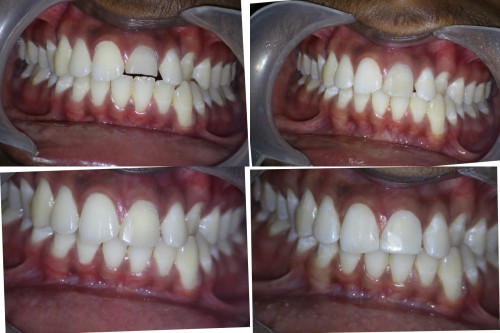

Pt 17yrs male presented with pain and discoloration of #9. After the Access prep,cleaning and shaping , temporary composite restoration was done. After 2 visits of CAOH dressing obutration completed and bleach placed for a week. Composite resoration done in #8 and repeated in #9.